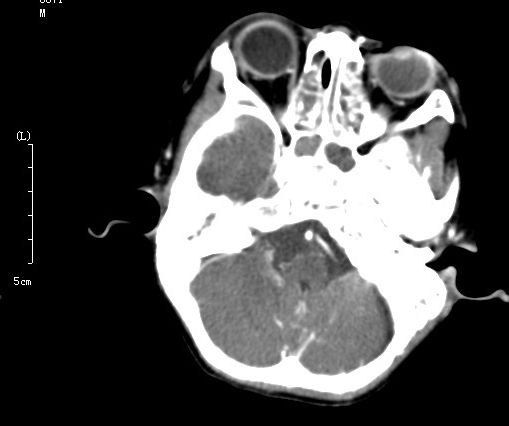

以下是引用dyqct在2006-8-27 13:58:00的发言:[br]位置太不标准。[br]双侧上颌窦、筛窦炎症。[br]看不出有海绵窦瘘的征象。[br]

以下是引用winter在2006-8-27 18:54:00的发言:[br]男,7岁,外伤后左眼搏动、疼痛。增强扫描左侧海绵窦增宽,考虑颈动脉海绵窦瘘,双侧上颌窦蝶窦筛窦内的考虑为积血才是。